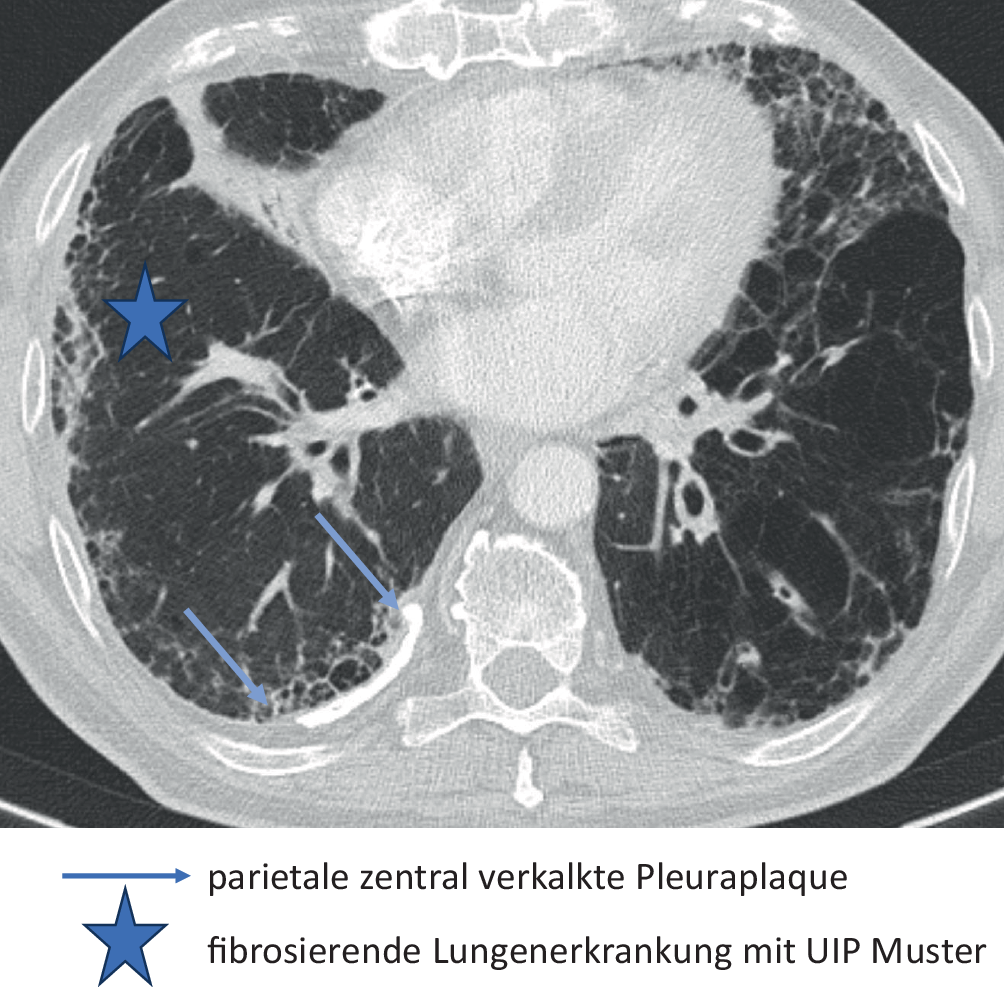

In der HRCT finden sich heute in Industrieländern überwiegend Parenchymmuster, die einem Initialstadium entsprechen. Das radiologische Bild ist zu diesem Zeitpunkt unspezifisch und nicht eindeutig einer Fibrose zuzuordnen (Tab. 6). Bei einer fortgeschrittenen Erkrankung sind differenzialdiagnostisch auch andere ILD mit UIP- oder NSIP-artigem Muster in Erwägung zu ziehen (Abb. 2). Bei bekannter Asbestfaserexposition kann in Deutschland eine fibrosierende Lungenerkrankung unfallversicherungsrechtlich dann mit überwiegender Wahrscheinlichkeit einer Asbestose zugeordnet werden, wenn bildmorphologische Kriterien einer asbestfaserbedingten Erkrankung der Pleura vorliegen und anderweitige Ursachen der pleuralen Verdickungen ausgeschlossen werden können.

Abb. 2

Asbestfaserbedingte Erkrankung von Lunge und Pleura

Benigne asbestfaserbedingte Erkrankung der Pleura BK 4103

Charakteristisch sind umschriebene spindel- oder tafelbergartige Areale mit einer hyalinen Fibrose der Pleura parietalis (sog. Pleuraplaques), die auch bei niedrigen Staubexpositionen ohne begleitende ILD auftreten können. Bei beidseitigem Auftreten sind sie bei Ausschluss anderweitiger Ursachen pathognomonisch. Eine Asbestfaserinhalation kann auch eine umschriebene oder langstreckige Verdickung der Pleura visceralis, eine Pleuritis, eine Hyalinosis complicata sowie Rundatelektasen induzieren (Tab. 7).